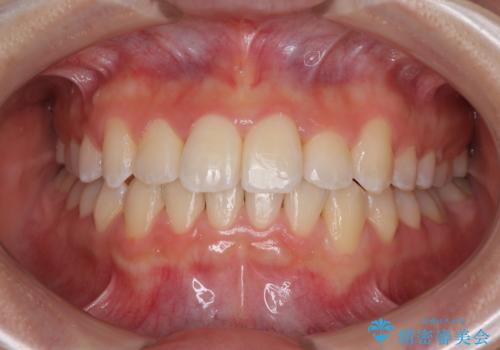

捻れて前に出ている前歯 ワイヤー装置での非抜歯矯正